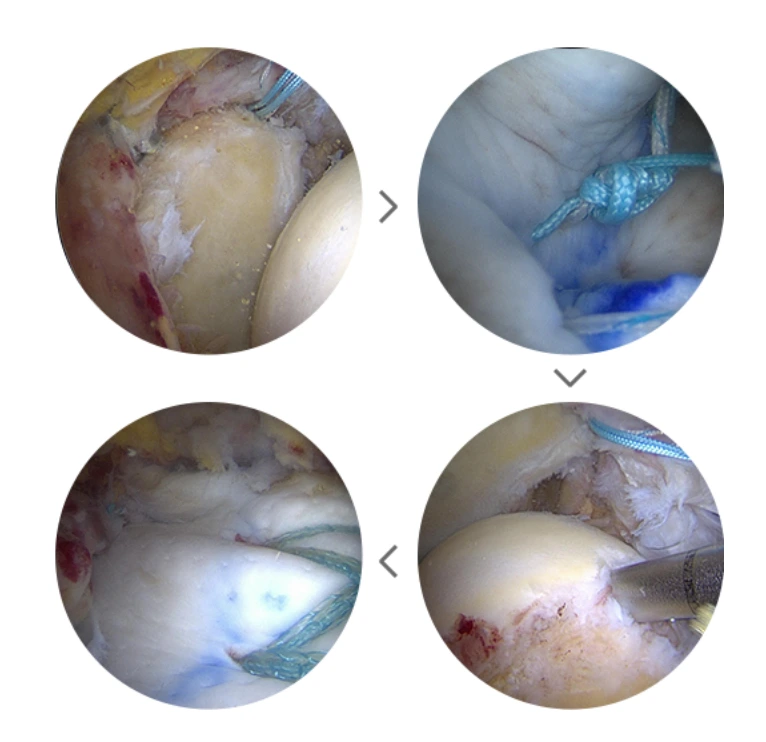

브릿지 이중 봉합술

어깨덮개뼈의 골극 아래에서 완전히 파열되어 내측으로 말려들어간 회전근개 힘줄이 붙어 있는 자리의 내측에 無나사 봉합사를 삽입해 특수 바늘을 이용해 힘줄을 봉합하는 수술입니다. 관절내시경을 통한 수술로 안정적이며 견고한 고정력, 그리고 재파열 위험이 낮은 것이 장점이에요.

브릿지이중봉합술.PNG